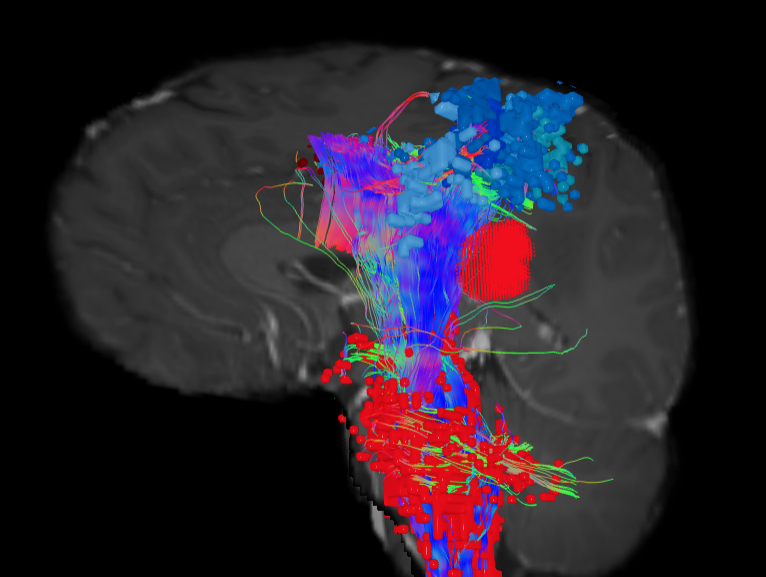

Connectomic-Guided Surgery

Real-time MRI during surgery to ensure complete and precise tumor removal while protecting healthy tissue.